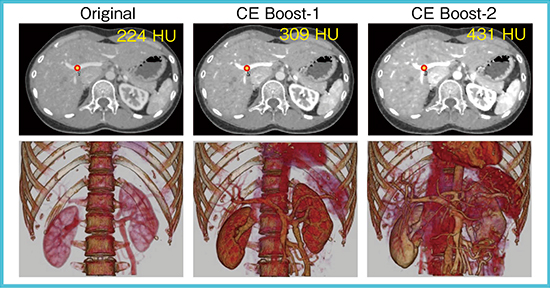

2.CE Boost

CE Boostは,非剛体位置合わせを応用してサブトラクション画像を造影画像に加算することで造影効果を向上させる技術である。CE Boost処理を1回だけでなく2回適用することで造影剤の感度をさらに上げることができる(図1)。

図1 CE Boostを利用した造影効果向上